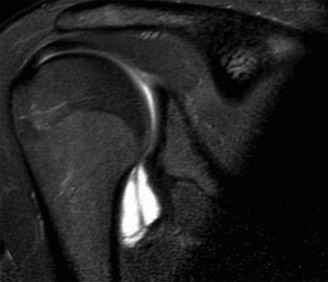

Image

The Glenoid Track Paradigm Application

The glenoid track is defined as the contact zone of the glenoid on the humeral head during maximum abduction and external rotation. The width of this track is approximately 83% of the intact glenoid width. However, in the presence of anterior glenoid bone loss, the glenoid track is narrowed by the exact width of the bony defect.

In this patient, the intact glenoid width was estimated at 28 mm. The 22% bone loss equated to a 6.1 mm defect. The native glenoid track (83% of 28 mm = 23.2 mm) was reduced by 6.1 mm, resulting in a functional glenoid track of 17.1 mm. The Hill-Sachs interval (the distance from the medial margin of the Hill-Sachs lesion to the medial margin of the rotator cuff footprint) was measured at 21 mm. Because the Hill-Sachs interval (21 mm) was greater than the functional glenoid track (17.1 mm), the lesion was classified as an "off-track" Hill-Sachs lesion. An off-track lesion will engage the anterior glenoid rim during abduction and external rotation, acting as a fulcrum to lever the humeral head out of the joint, guaranteeing failure of an isolated arthroscopic Bankart repair.

Magnetic Resonance Arthrography Evaluation

Magnetic Resonance Arthrography (MRA) was also performed to evaluate the capsulolabral complex, rotator cuff, and articular cartilage. The MRA confirmed the complete avulsion of the anterior-inferior labrum with a periosteal sleeve avulsion, but without significant medial displacement (ruling out an ALPSA lesion). The anterior band of the IGHL was attenuated but remained attached to the humeral neck, ruling out a Humeral Avulsion of the Glenohumeral Ligament (HAGL) lesion. The rotator cuff tendons were intact, and there was no evidence of significant chondral delamination or osteoarthritis (Kellgren-Lawrence Grade 0).